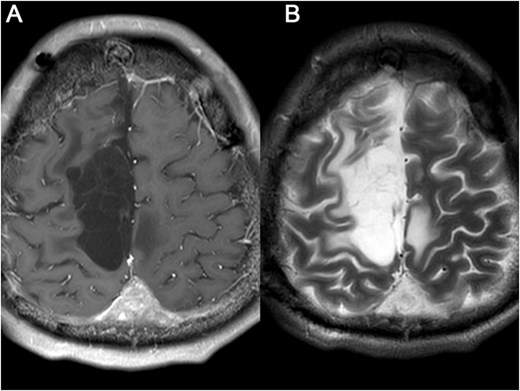

A 23-year-old male presented to our hospital with a 3-day history of episodic left upper limb paralysis. Upon admission, he reported progressive left lower limb motor incoordination, temporal visual field defects in the left eye, bilateral vision,deterioration, and bilateral olfactory hypesthesia over the preceding 3 months. Three days prior to admission, he experienced sudden-onset left upper limb paralysis lasting ~10 minutes before spontaneous resolution. Cranial magnetic resonance imaging (MRI) revealed a giant meningioma (>8 cm in diameter) causing extensive compression of adjacent structures, with marked heterogeneous enhancement on contrast imaging (Fig. 1). Preoperative intracranial vascular embolization was performed, followed by tumor resection via a bifrontal-parietal approach 1 day later (Fig. 2). Intraoperative findings confirmed a tumor >8 cm in diameter with cranial bone erosion (Fig. 3). Postoperatively, the patient developed transient bilateral lower limb paralysis (muscle strength grade 0) on Day 1, which resolved completely within one month. Histopathological analysis demonstrated features consistent with atypical meningioma: sheet-like growth pattern, increased nuclear-to-cytoplasmic ratio, prominent nucleoli, focal necrosis, and immunohistochemical staining showing Vimentin(+), SSTR2(+), PR(+), EMA(−), and a Ki-67 proliferation index of 5%–10%. The patient underwent gamma knife radiosurgery at 6 months and 1 year postoperatively. Three-year follow-up MRI showed no tumor recurrence or significant progression of residual lesions (Fig. 4), with significant improvement in visual acuity, hearing, and visual field deficits.

Brain MRI was re-examined after 5 months (A) and 17 months later (B), respectively, and showed that the residual tumor had not progressed and no other recurrence lesions were found.